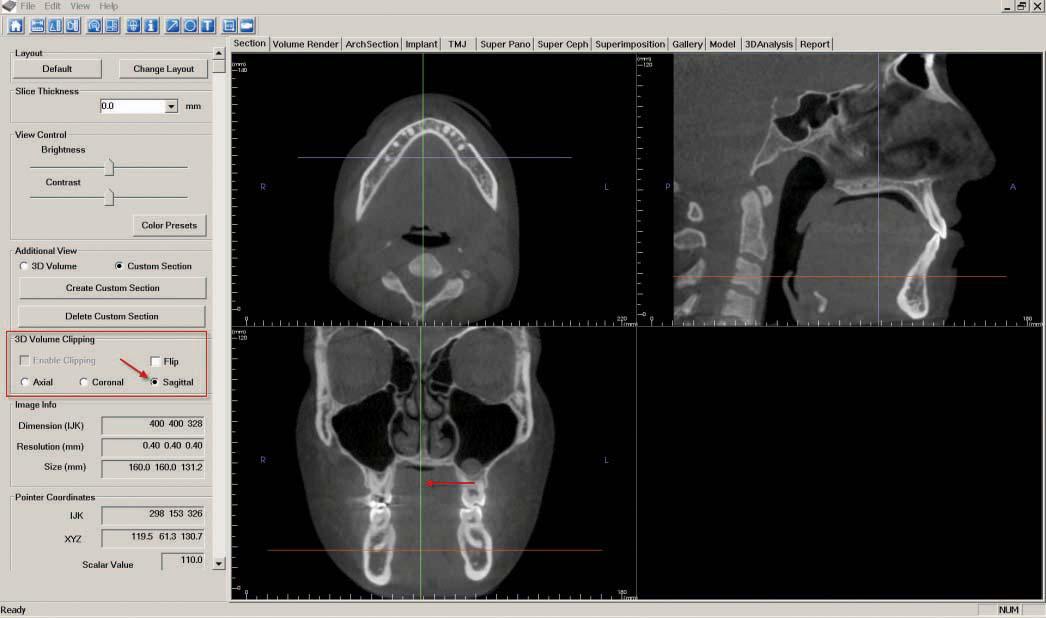

c. The "Coronal Slice" is created by navigating to the "Section" tab. First, ensure the patient is correctly oriented. To adjust the orientation, click the "Reorientation" icon at the top of the screen.

Once the orientation is correct, adjust the orange line in the bottom left image until the top left image shows a clear view of the lower arch. Next adjust the purple line in the upper left image while looking at the image below until there is a clear coronal slice of the first molars.

In the "3D Volume Clipping" section on the left-hand side of the screen, select "Coronal."

If desired, click the "Toggle Cursor Visibility" icon to remove reference lines. As described in step 7, "Capture to Gallery" and select "Coronal" in the "Select Image to Capture" pop-up window. Click "OK," then name the image "Coronal Slice."

d. To create the "Axial Slice," stay in the "Section" tab and adjust the orange line in the lower left image until the upper left image shows a clear view of the mandibular bone. In the "3D Volume Clipping" section on the left-hand side of the screen, select "Axial."

e. If desired, click the "Toggle Cursor Visibility" icon to remove reference lines. As described in step 7, "Capture to Gallery" and select "Axial" in the "Select Image to Capture" pop-up window. Click "OK," then name the image "Axial Slice."

f. The "Sagittal Slice" is also created in the "Section" tab. Adjust the green line in the center of the bottom left image until the upper right image shows a clear view of the right centrals. In the "3D Volume Clipping" section on the left-hand side of the screen, select "Sagittal."

If desired, click the "Toggle Cursor Visibility" icon to remove reference lines. As described in step 7, "Capture to Gallery" and select "Sagittal" in the "Select Image to Capture" pop-up window. Click "OK," then name the image "Sagittal Slice."